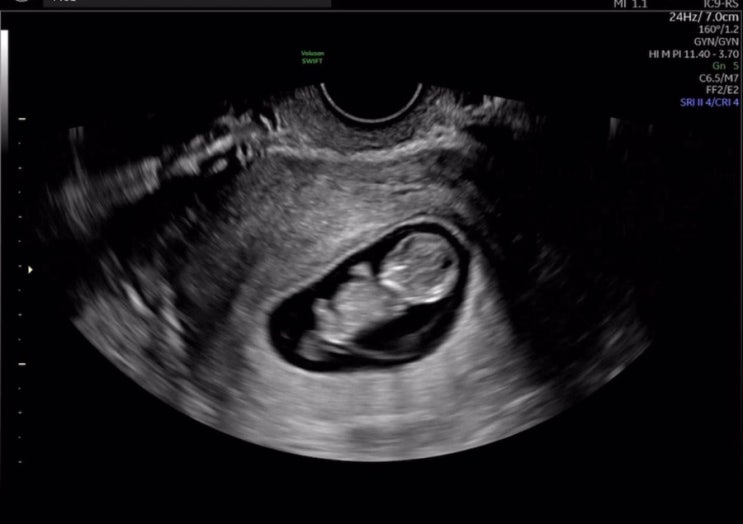

34w+5d 나 자연분만 할 수 있을까.. (머리 큰 아기)

오늘 정기검진을 받고 또 한 번 겁을 호달달 먹은 산모입니다 까치 누구 닮아서 이렇게 장사만치로 잘 자라...